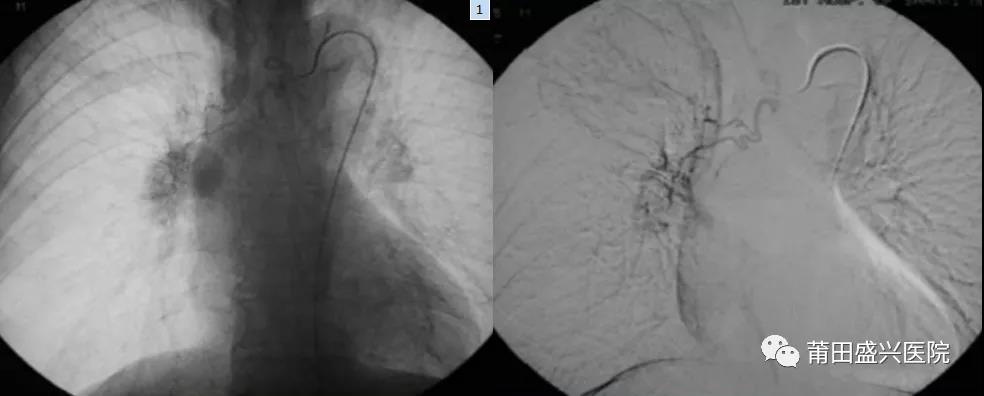

肺癌動脈灌注化療+栓塞